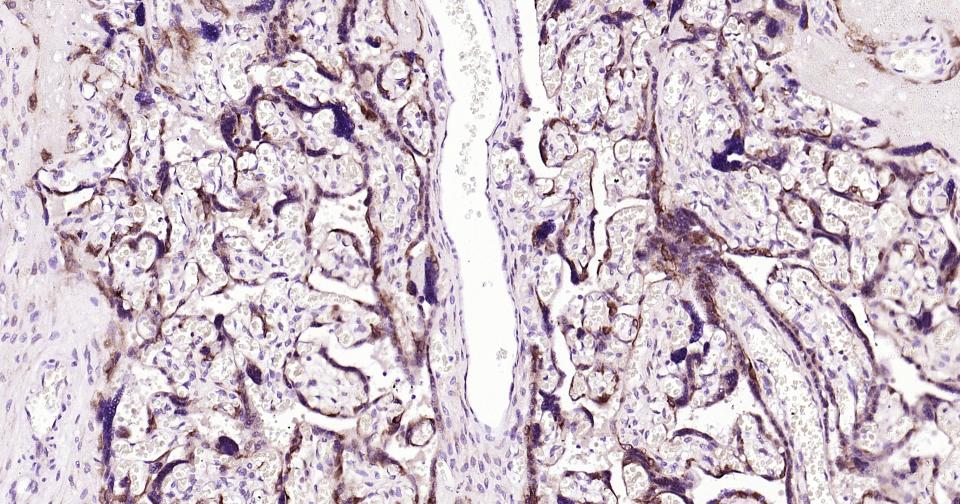

Paraformaldehyde-fixed, paraffin embedded Human Placenta; Antigen retrieval by boiling in sodium citrate buffer (pH6.0) for 15 min; Antibody incubation with MSI2 Monoclonal Antibody, Unconjugated(bsm-61244R) at 1:200 overnight at 4°C, followed by conjugation to the bs-0295G-HRP and DAB (C-0010) staining.

Paraformaldehyde-fixed, paraffin embedded Human Placenta; Antigen retrieval by boiling in sodium citrate buffer (pH6.0) for 15 min; The section was incubated with MSI2 Monoclonal Antibody, Unconjugated (bsm-61244R) at 1:200 overnight at 4°C. Followed by conjugated Goat Anti-Rabbit IgG antibody (Red, bs-0295G-BF594), DAPI (blue, C02-04002) was used to stain the cell nuclei.